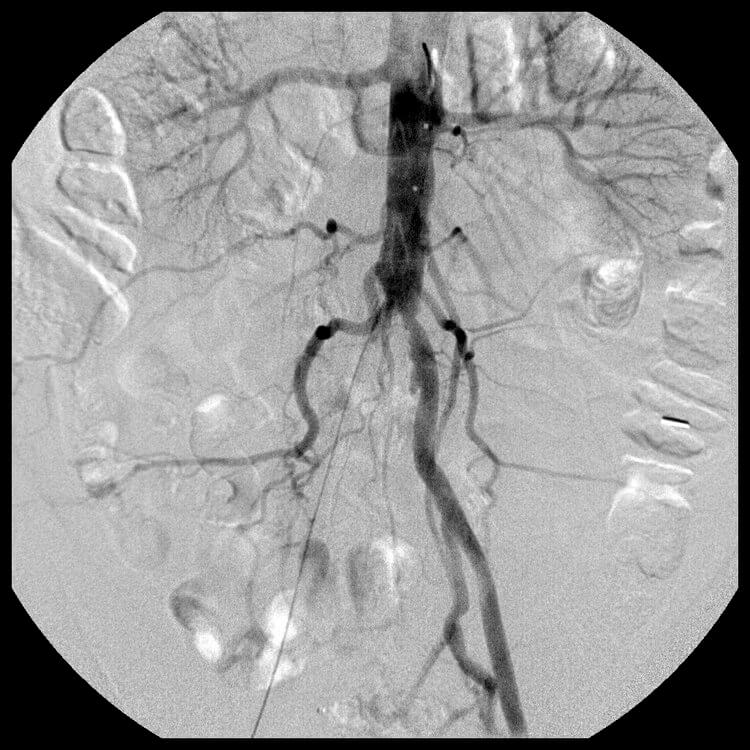

Early image from an abdominal aortogram performed from right common femoral artery access. This demonstrates the occlusion of the right common iliac artery and mild stenosis at the origin of the left common iliac artery. -

Later image from the abdominal aortogram showing reconstitution of the right external iliac artery. -